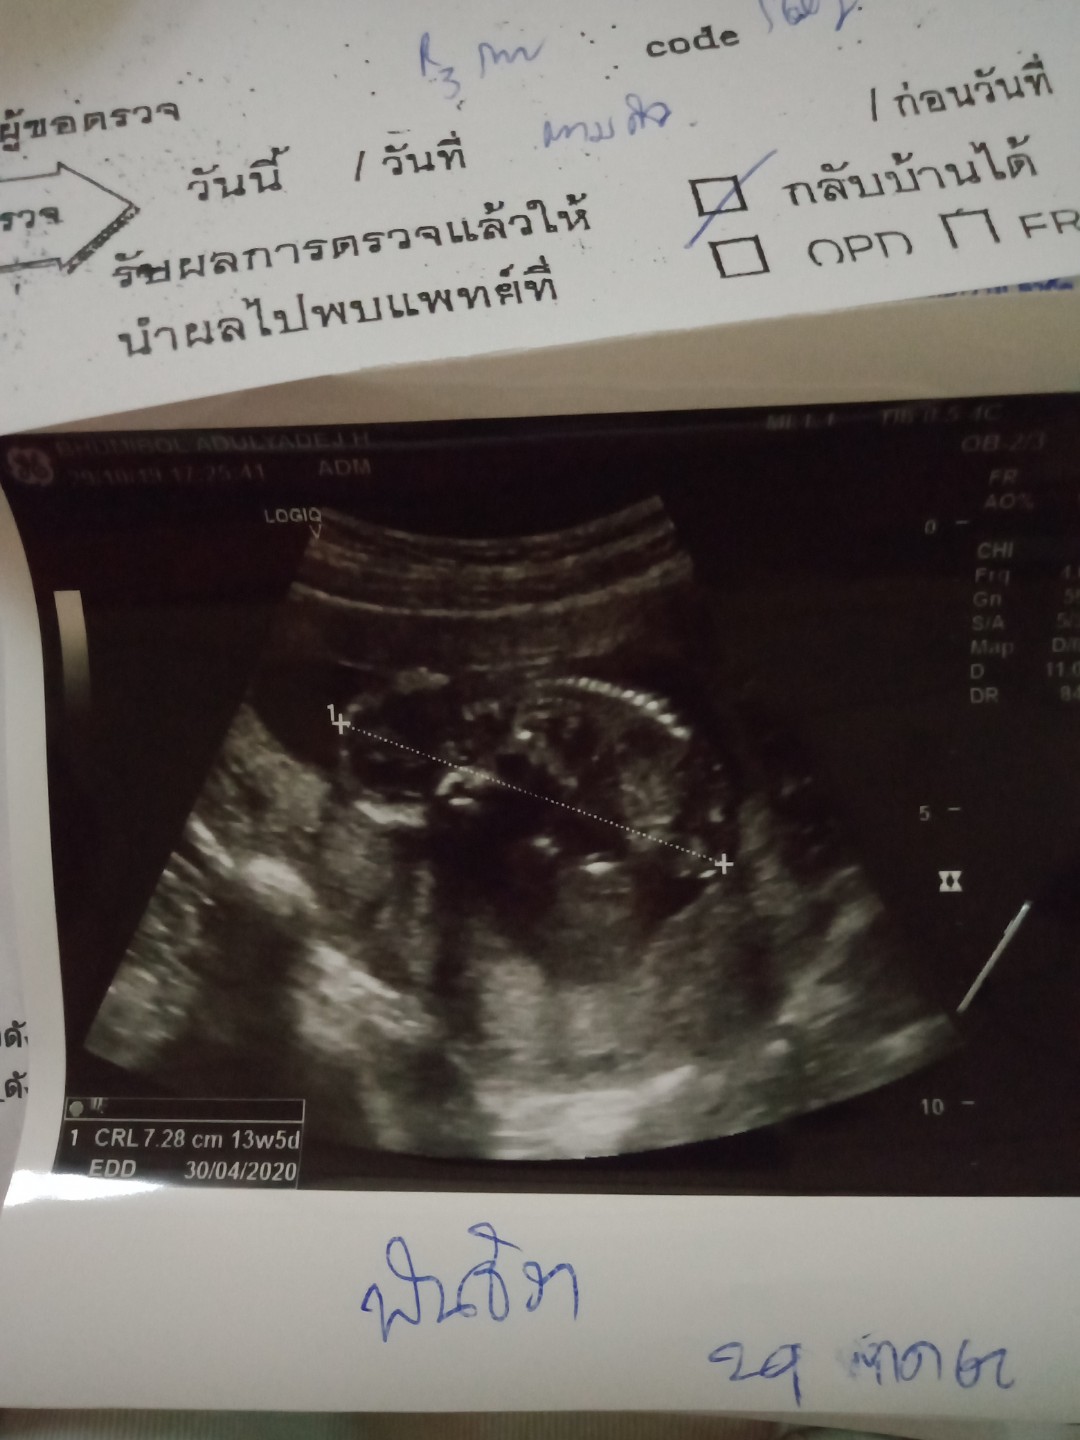

ซาวด์ตอน3เดือนค่ะ